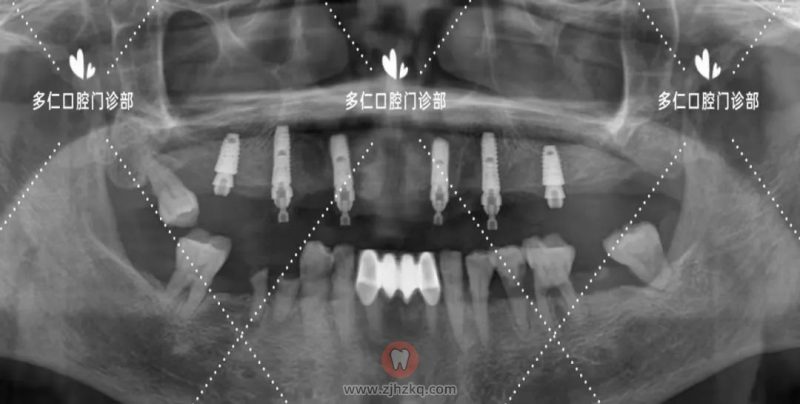

术后全景片